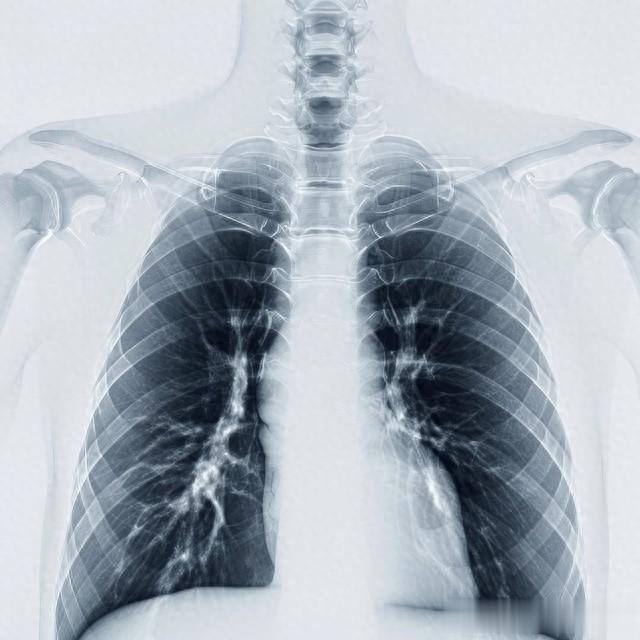

肺癌患者CT